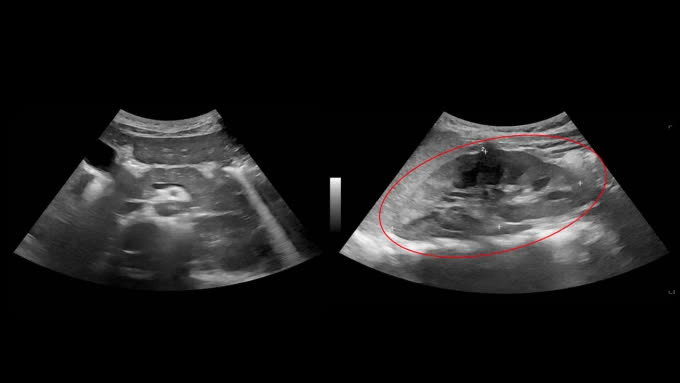

Tại đây các bác sĩ xét nghiệm nước tiểu cho bệnh nhi phát hiện đạm niệu cao, có hồng cầu (tiểu ra máu) kèm tổn thương ống thận. Kết quả siêu âm ổ bụng, xét nghiệm lupus ban đỏ, phát hiện bệnh tiến triển nặng khiến thận bị tổn thương, đề nghị sinh thiết để chẩn đoán thêm.

| Kết quả siêu âm ổ bụng cho thấy gan bệnh nhân có dấu hiệu tổn thương, cần sinh thiết để chẩn đoán thêm. Ảnh BVCC |